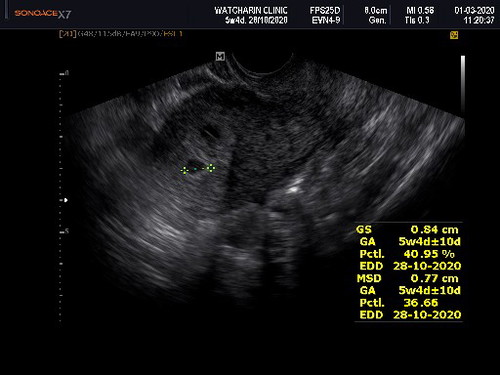

เคยท้องนอกมดลูก 1 ครั้งค่ะ ตอนนั้นฉีดยาสลายไป หลังจากนั้นอีก 5 ปี ค่อยปล่อยมีลูก ปัจจุบันเพิ่งตั้งท้องประมาณ 6W อัลตร้าซาวด์เจอถุงตั้งครรภ์ในมดลูก แต่บางครั้งชอบมีอาการปวดจี๊ดๆข้างที่เคยท้องนอกมดลูก และปวดหลังล่าง อยากสอบถามว่าเป็นไปได้ไหมคะที่เราจะท้องนอกมดลูกพร้อมกับท้องในมดลูกด้วย แม่แอบกังวลค่ะ